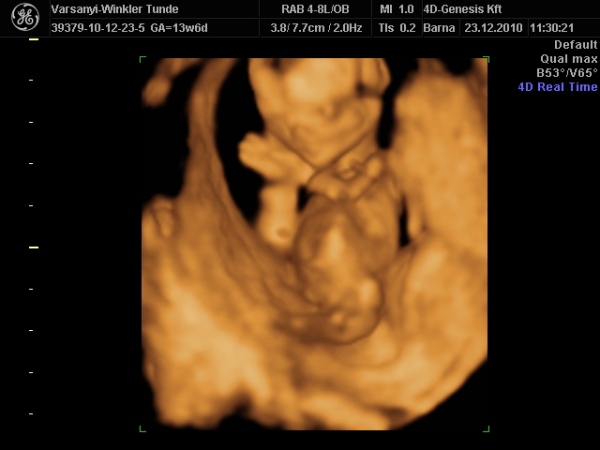

)2010.12.23 11:37